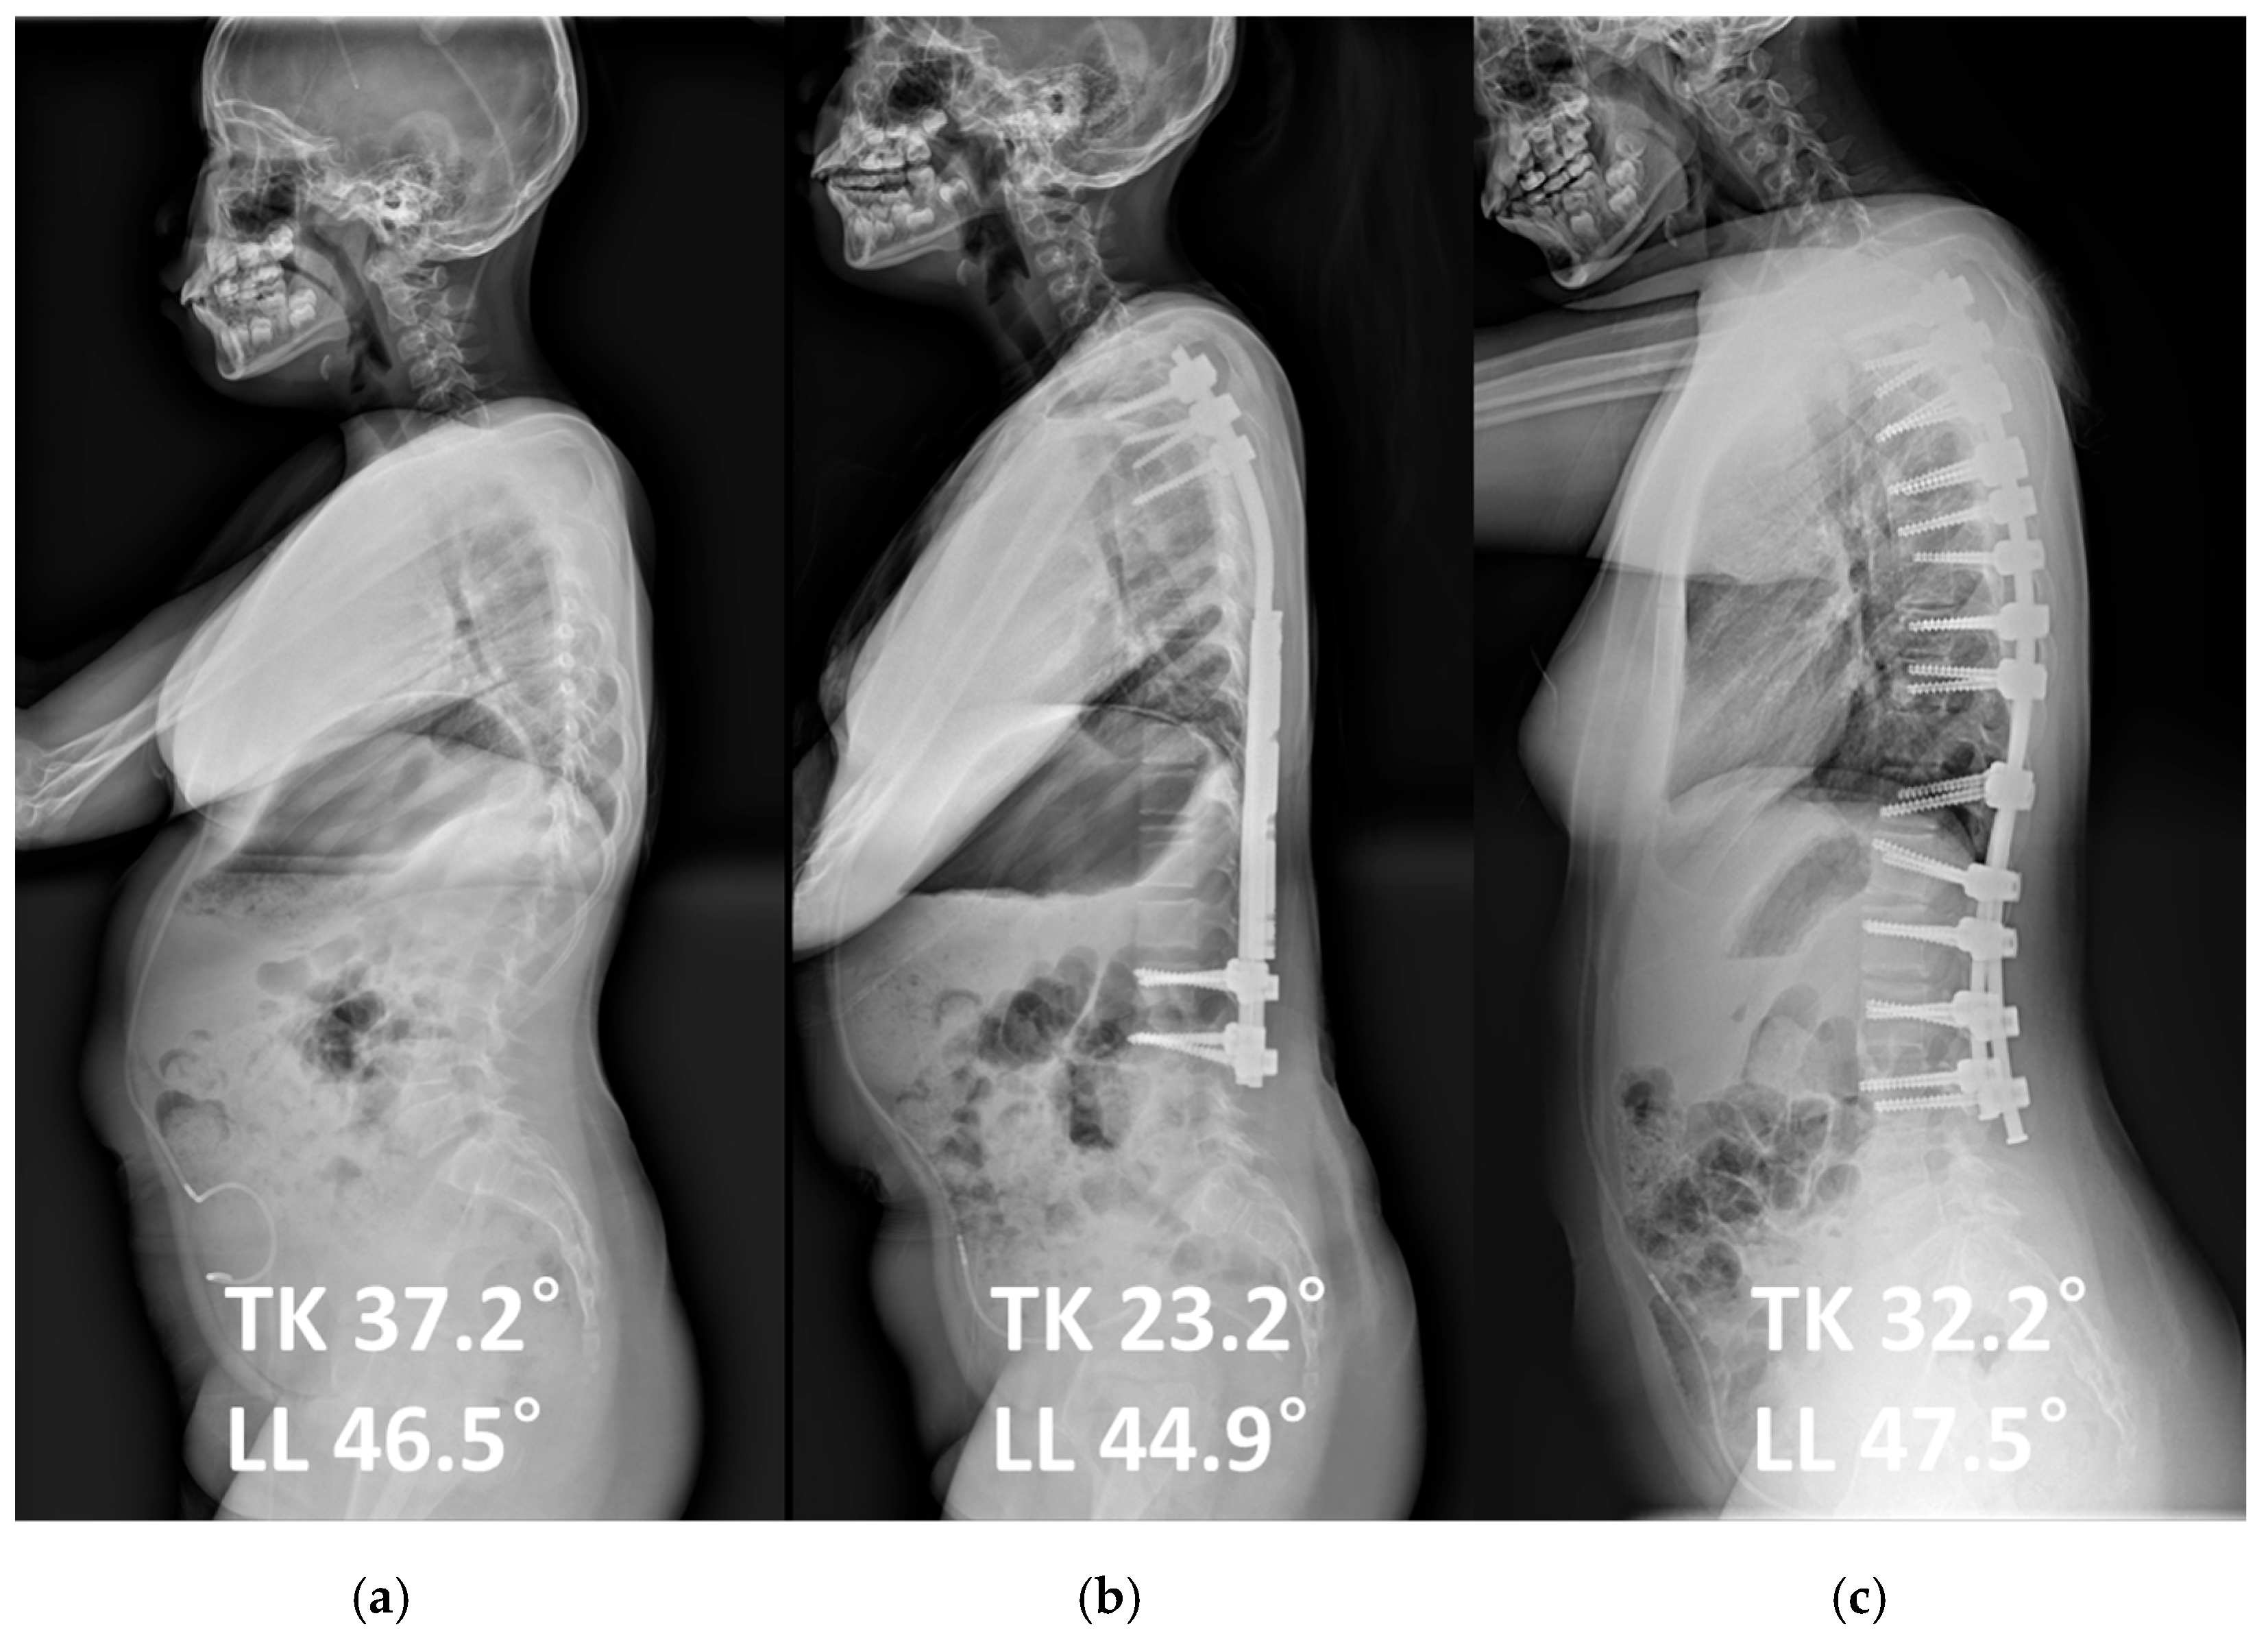

| Thoracic kyphosis (°) | 28.4 ± 12.9 | 34.6 ± 10.6 | 0.268 |

| Lumbar lordosis (°) | 43.5 ± 15.2 | 49.0 ± 11.7 | 0.399 |

| Δ Thoracic kyphosis (°) | −11.9 ± 16.4 | 0.1 ± 11.9 | 0.088 |

| Δ Lumbar lordosis (°) | −4.3 ± 12.9 | −4.9 ± 19.8 | 0.942 |